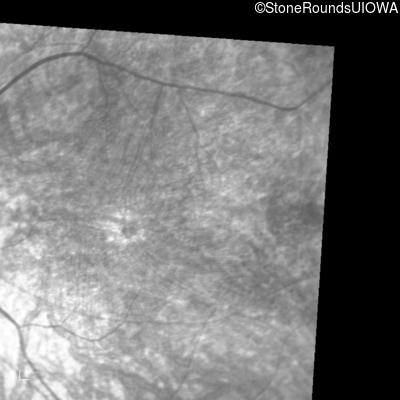

Infrared Fundus Photograph - Right - 10/300 sc

Exemplar

Infrared Fundus Photograph - Left - 10/300 sc